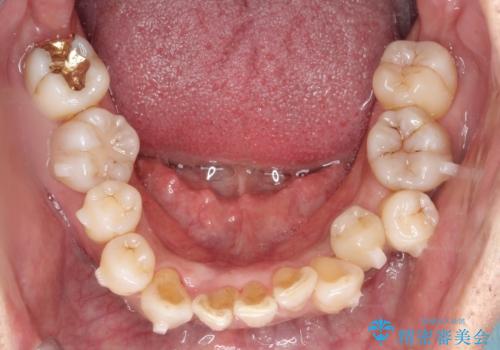

- 50代の患者様で、右上の八重歯と歯並びの乱れを気にされてご来院されました。特に、すでに装着されている前歯のセラミックブリッジを外したくないという強いご希望がありました。精密な検査の結果、八重歯を治すためのスペースが不足しているため、右上の4番目の歯(小臼歯)を抜歯し、そのスペースを利用して歯並び全体を整える治療計画を立案。装置には目立たないインビザラインを採用し、ブリッジを温存しながら八重歯の改善を目指しました。

今回の治療で最も重要だったのは、患者様のご要望通り既存のセラミックブリッジを外さずに矯正を進める点でした。計画通り右上の小臼歯を抜歯し、透明なインビザラインを使用して抜歯スペースを閉じながら、八重歯を正しい位置へ移動させました。ブリッジの形態と調和するに、他の歯の移動を工夫をすることで、複雑な条件をクリア。治療の結果、長年気にされていた八重歯が解消され、見た目が大きく改善しました。50代からでも、ご自身の要望を叶えながら、美しく機能的な歯並びを獲得していただけました。